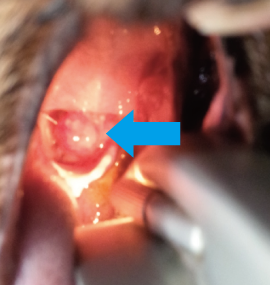

癌の進行状況によって治療は変わっていきます。

症状は時間が経つにつれて悪化していきます。以前は癌というと治療法はなく、亡くなってしまう病気と思われていました。しかし、獣医療の進歩により癌の中には完全に取り除いたり(根治治療)、生涯に渡ってコントロールすることで痛みや苦しみを和らげ(緩和療法)、生活の質(QOL)を保てたりする可能性が広がり、治療も日々変化しています。